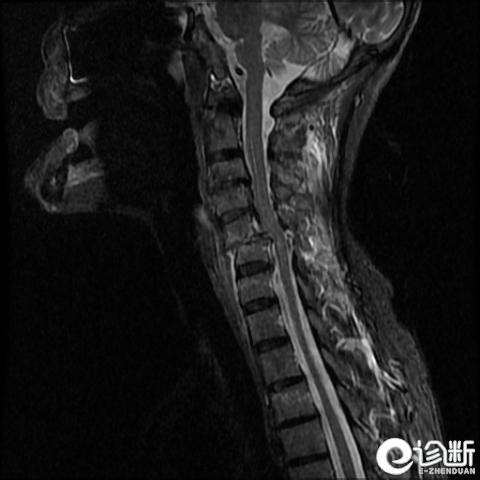

颈椎骨折

MRI:评估软组织

Hx:创伤史。疼痛,活动后加重;麻木及无力

PE:压痛,“台阶征”及神经或脊髓体征。直肠及生殖系统检查!